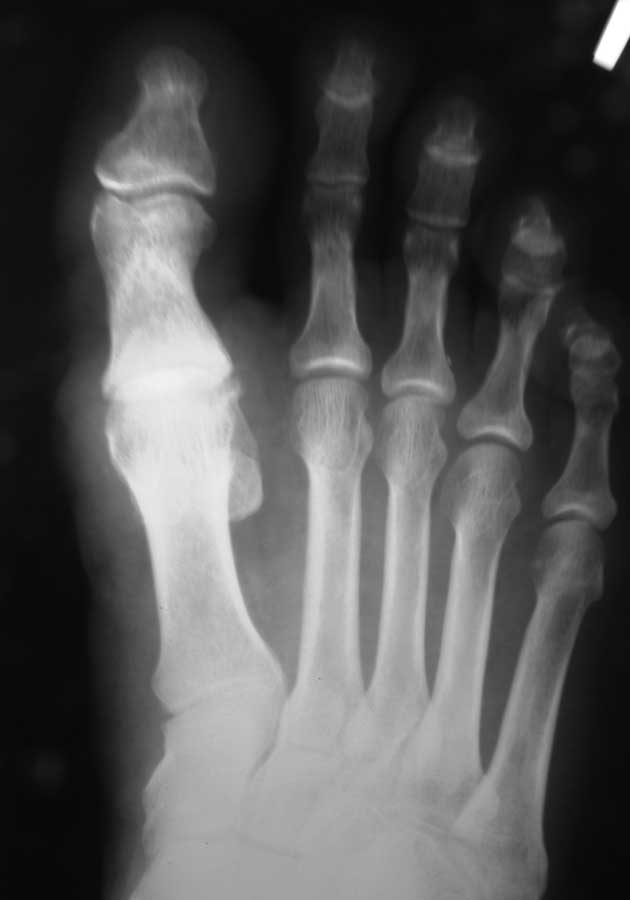

Здравствуйте, коллеги. Помогите с тактикой дальнейшего лечения.Мужчина 52 года, активный физически. В марте 2012 оперирован по поводу ДОА плюсне-фалангового сустава 1 пальца, сделана резекция основания основной фаланги и остеофитов головки плюсневой кости. Послеоперационное лечение: массаж, физиотерапия. В настоящее время беспокоят сильные боли в суставе, сохраняется ограничение движений. Дальнейшая тактика: артродез ПФС?, Эндопротезирование ПФС?, повторная резекция основной фаланги? Мнения наших коллег разделились. На фотографиях: вид стопы в настоящее время, рентгенограммы до операции, после операции, в настоящее время. Прошу прощения за неважное качество снимков.

Просто удаление остеофитов не приводит к желаемому результату. Необходимо резецировать до 1/3 суставной поверхности головки, основание очистить от остеофитов с тыльной поверхности.

Любой из рассматриваемых Вами вариантов имеет право на жизнь. Наиболее вероятная причина болей - слишком экономная резекция фаланги: адекватная декомпрессия сустава не достигнута. Протезирование 1 ПФС у молодого активного физически мужчины предполагает ревизию уже через несколько лет. Так что артродез или повторная резекция основной фаланги - равнозначные оптимальные варианты.

Причинами неудовлетворительного результата могли стать следующие: 1) недостаточная величина резекции основной фаланги и 2) "стирание" оставшегося хряща головки 1 ПК опилом фаланги. В своей практике обычно убираем больше кости (примерно 1/4 - 1/3 длины фаланги), опил моделируем, укрываем лоскутом капсулы или Артелоном (специальный биодеградируемый скользящий материал).

2) повторная резекция основания фаланги (опил необходимо укрыть), круговой релиз 1 ПФС. Ранняя разработка движений в суставе.

Наилучшим вариантом представляется вар. 2, так как сохраняется собственная головка 1 ПК, которая хорошо переносит нагрузки (а в фазу заднего толчка на неё приходится до 70% веса человека). Имеем достаточно много отдалённых результатов: амплитуда движений в 1 ПФС 30 - 45 градусов, болевой синдром не беспокоит.